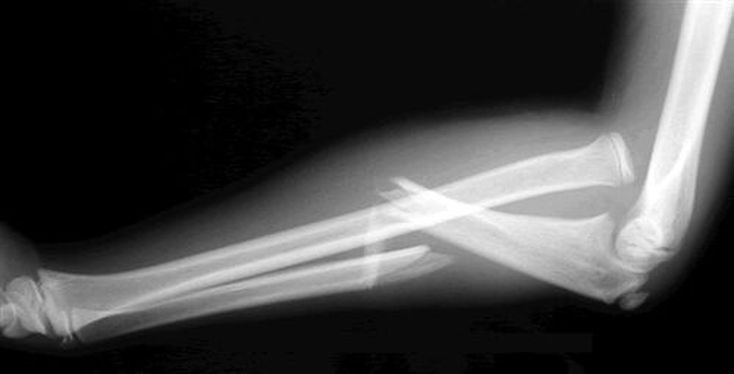

Galeazzi fracture